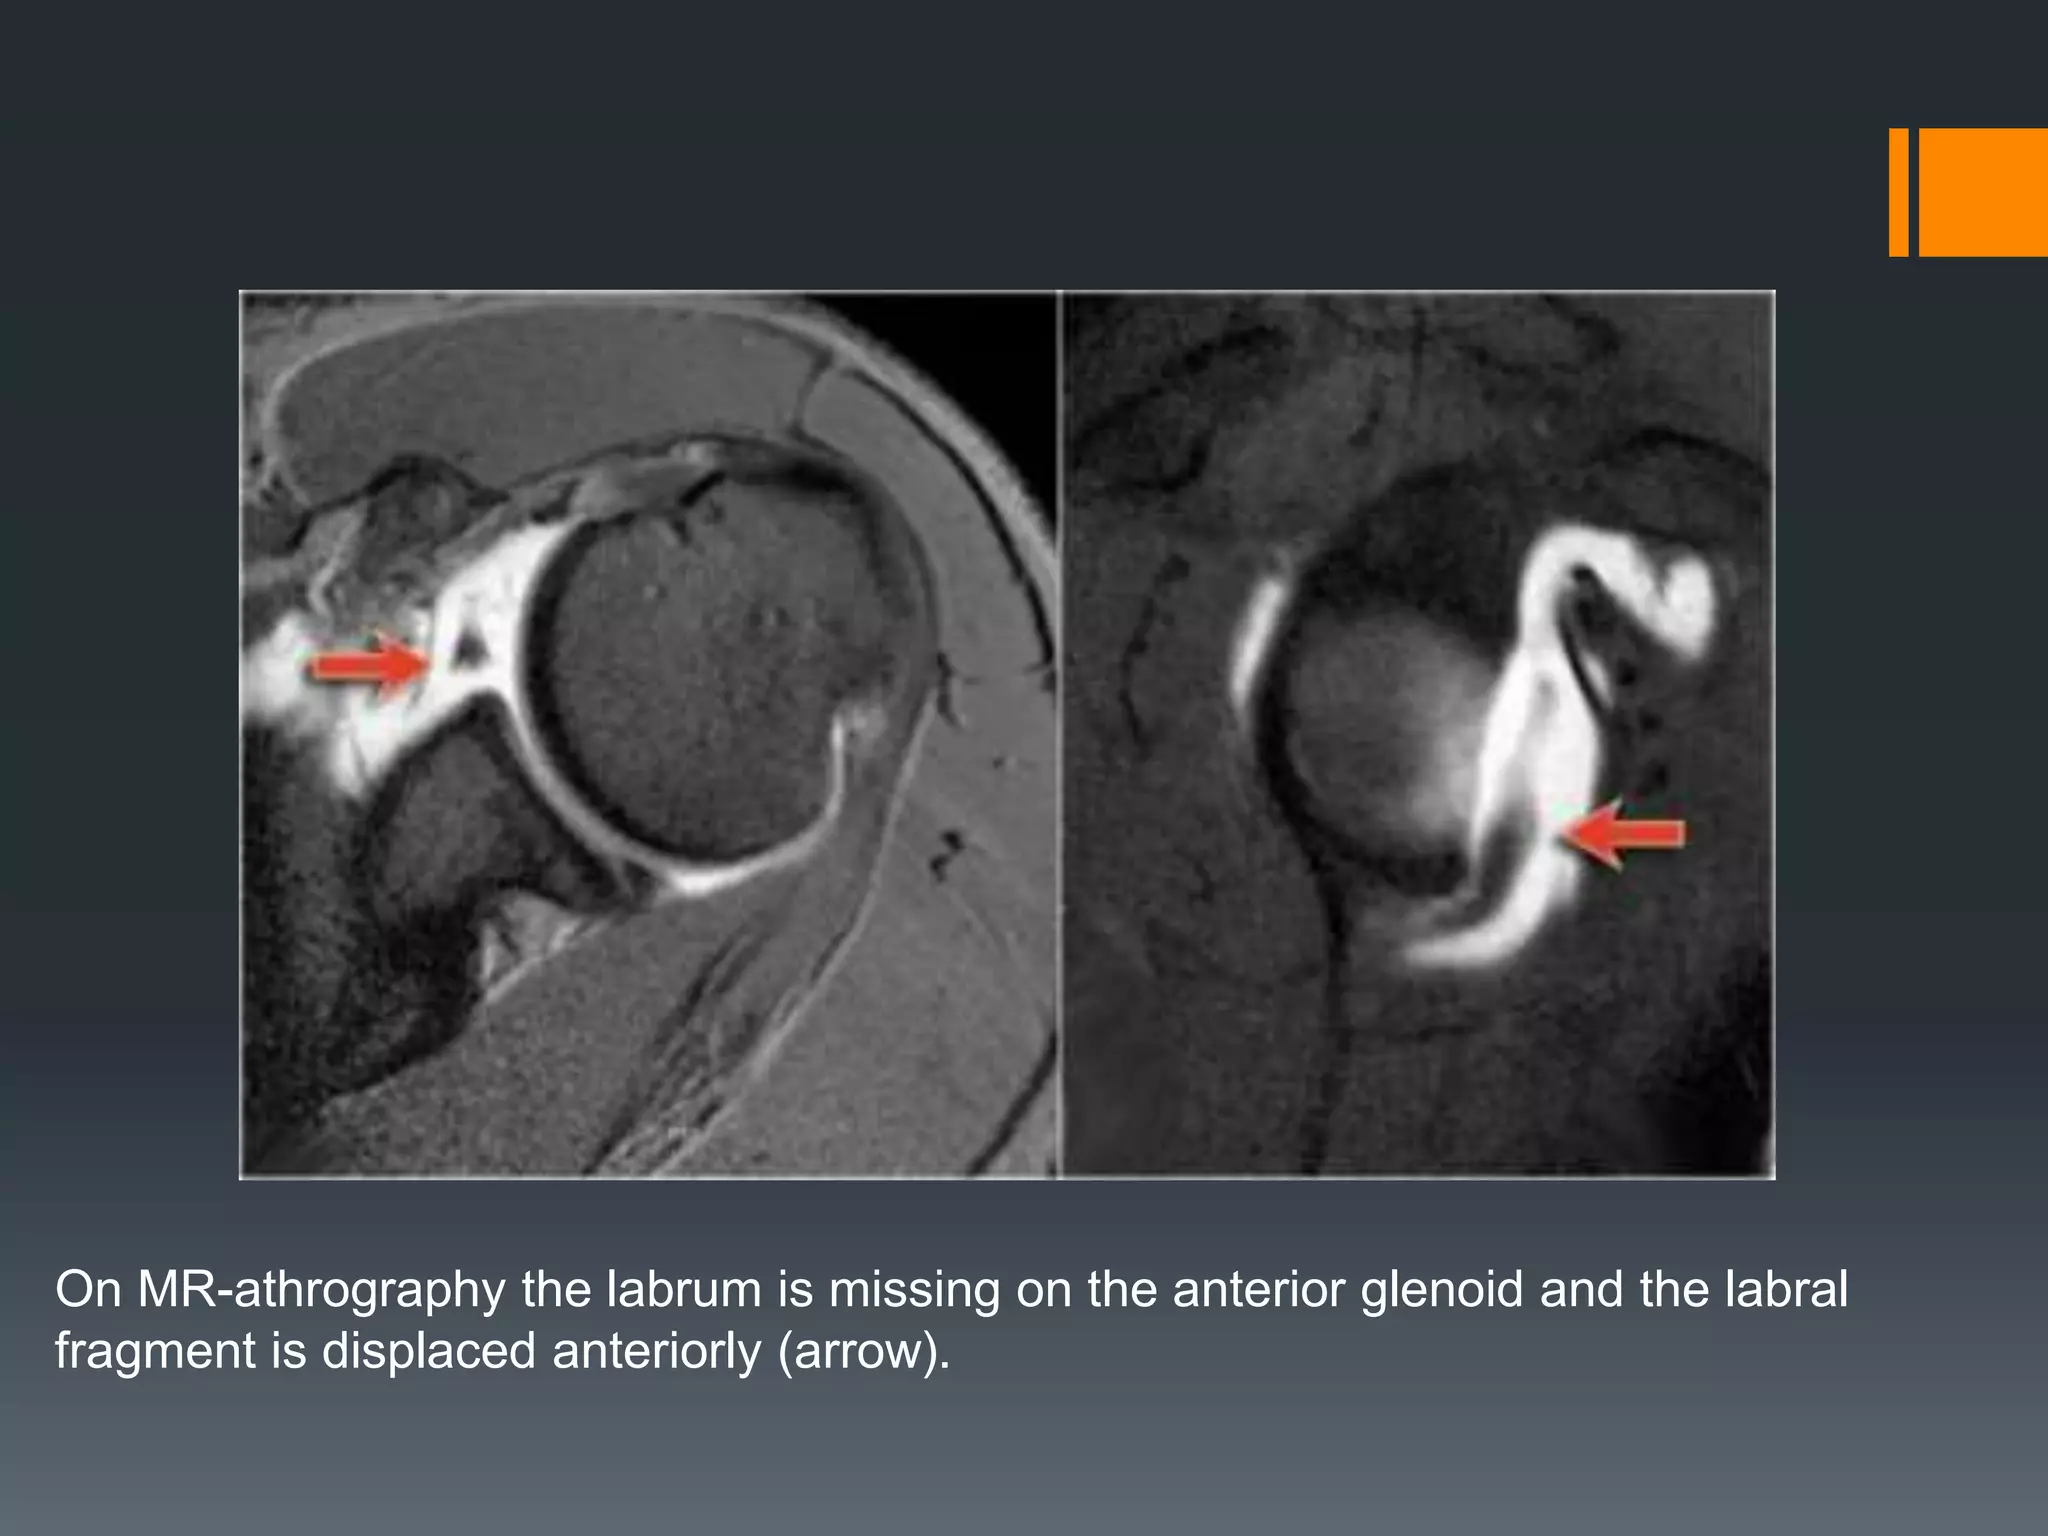

Bankart lesion

Bankart lesions are labral tears without an osseus fragment.

MR arthrography or arthroscopy are optimal to diagnose Bankart or Bankart-like

lesions.

There is a detachment of the anteroinferior labrum (3-6 o'clock) with complete

tearing of the anterior scapular periosteum.

The arrow points to the disrupted periosteum.

On MR-athrography the labrum is missing on the anterior glenoid and the labral

fragment is displaced anteriorly (arrow).